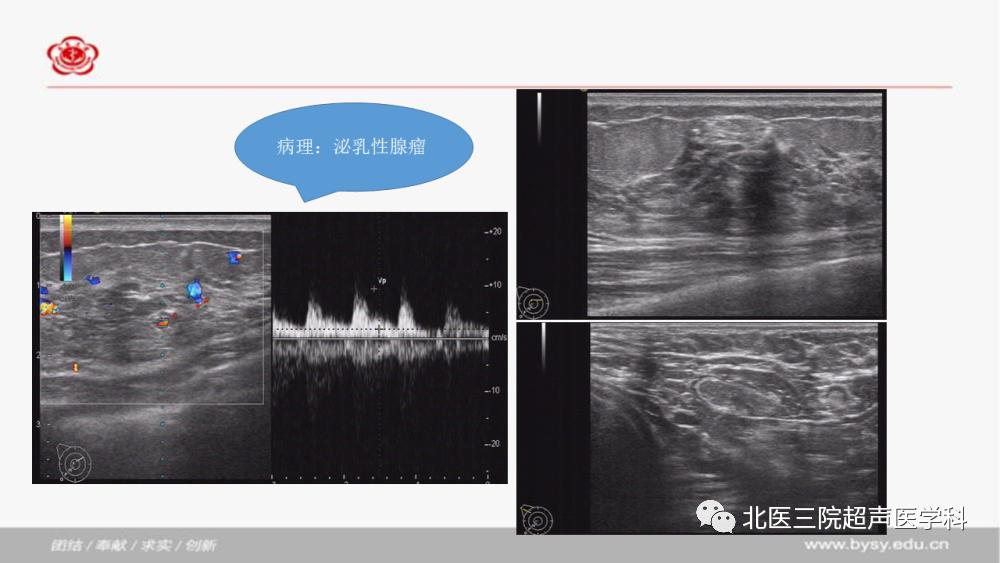

泌乳性腺瘤

发布时间:2020-06-06 点击数: